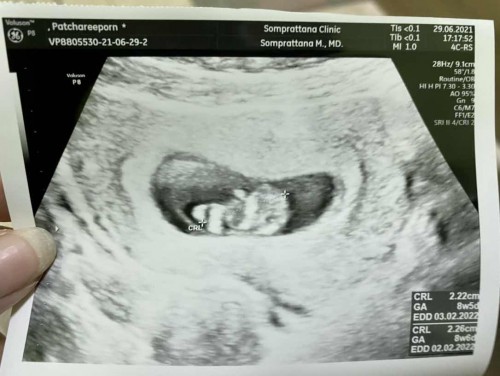

ไม่ต้องกังวลนะคะคุณแม่ รอบประจำเดือนล่าสุดกับรอบไข่ตกจริง อายุครรภ์อาจห่างกันได้ค่ะ ฟังคุณหมอนะคะ

ของเราเป็นเหมือนกัน หมอบอกว่า ไข่ตกคลาดเคลื่อน ให้นับจากเครื่อง กับ ที่หมอวิเคราะห์แจ้งอีกที